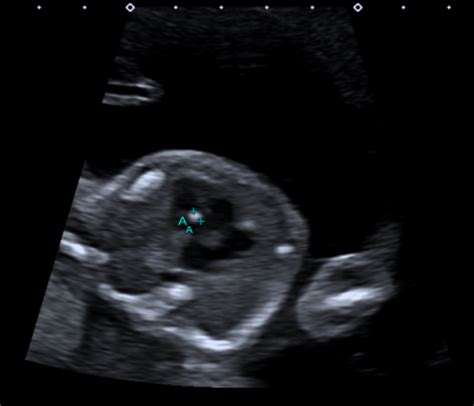

Alright, let’s get real about the 20-week anatomy scan, often called the mid-pregnancy ultrasound. This is a pretty major milestone in your pregnancy journey , guys. It’s not just about getting a sneak peek at your baby’s face (though that’s super fun!); it’s primarily a detailed examination to check on your baby’s development and anatomy. The sonographer is meticulously measuring bones, looking at organs, checking the heart’s chambers, and making sure everything is forming as it should be. Now, when people use terms like ‘IOSC H OWSC Common’ on Reddit, they’re often referring to soft markers or incidental findings . These are observations during the ultrasound that might be slightly outside the typical range but don’t necessarily indicate a problem. Think of them as tiny flags that might prompt a closer look, but in many cases, they turn out to be completely insignificant variations. Some of the most commonly discussed soft markers that might lead to such forum chatter include:

• Echogenic Intracardiac Foci (EIFs): These are bright spots seen in the baby’s heart chambers. They are incredibly common, especially in certain populations, and in most cases, they have absolutely no impact on the baby’s heart function or overall health. They often disappear on subsequent ultrasounds.